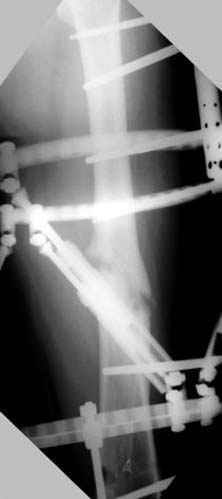

пластическая модель; и коррекция бедра аппаратом Илизарова.

Почему не замена гвоздя с рассверливанием, а аппарат?

хотя даже если бы и инфекция , то nail exchange с рассверливанием канала - вариант дебрайдмента) Я думаю, что последовательность развития событий:

Узкий к-м канал - тонкий гвоздь- усталостный перелом дистальных винтов - развитие нестабильности и как ее результат остеолиз вокруг гвоздя - деформация анатомической оси бедра. Похоже, что я понял почему аппарат, а не новый гвоздь:-)

ЕТ - Изначально костно-мозговой канал бедра был узкий, дальнейшее его рассверливание ещё больше скомпрометирует прочность бедра( латеральный кортекс дистального отломка уже истончен), приведет к дефекту наружной стенки - хотя это только мои догадки - хотелось бы знать мнение Джолдаса о выбранной тактике.